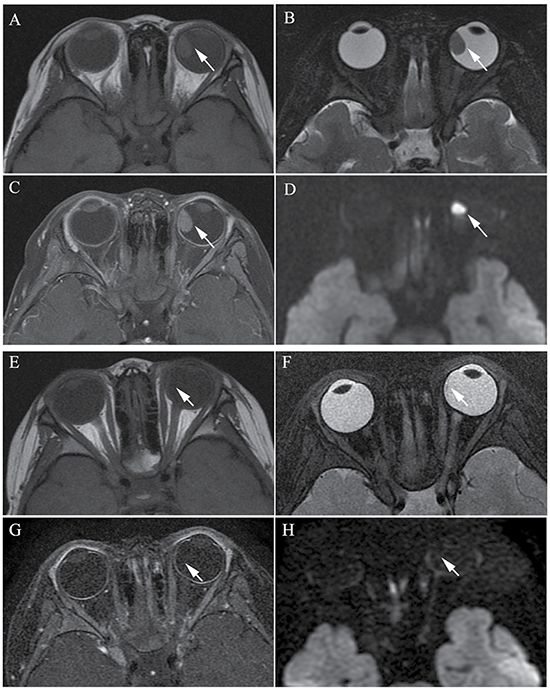

Figure 2: Clinically diagnosed retinoblastoma in a 44-month-old female (patient 2). (A–H) The orbital origin of the tumor was located in the equator of the left globe with the tumor location far from the optic disk, demonstrating a slightly higher signal intensity than the ocular fluid (arrow) in axial T1-weighted MRI (A), low signal intensity (arrow) in the axial T2-weighted MRI (B) and moderate enhancement of the retinoblastoma (arrow) in the axial contrast-enhanced T1-weighted, fat-saturated MRI (C). The axial DWI (D) shows restricted diffusion (arrow) in the tumor. (E–H) A small amount of the residual tumor foci is shown (arrow) in the axial T2-weighted MRI (F) after three cycles of IAC. The axial contrast-enhanced T1-weighted, fat-saturated MRI (G) shows non-enhancement of the residual tumor foci. The axial DWI (H) shows low signal intensity of the residual tumor foci (arrow).

The size of the tumors was obviously diminished after IAC in all 60 eyes, including the mean maximum diameter (t = 19.15; P < 0.001), the mean thickness (t = 18.49; P < 0.001), and the maximum cross-sectional area (t = 21.35; P < 0.001) (Figure 1 and Figure 2). Both group D and group E showed a significant difference in tumor size after IAC. There was no significant difference between the patients of group D and group E in the tumor size before or after treatment.

Among the 60 eyes, compared to pretreatment, 51 tumors with moderate enhancement decreased to non-enhancement (Figure 1 and Figure 2) (n = 46; 90.2%) or slight enhancement (n = 5; 9.8%), and the other nine tumors changed from slight enhancement to non-enhancement (n = 9; 100%). Nodular enhancement of postlaminar optic nerves observed in six (10%) affected eyes before IAC disappeared after IAC (Figure 3).

Figure 3: Clinically diagnosed retinoblastoma in a 16-month-old male (patient 3). Oblique sagittal contrast-enhanced T1-weighted, fat-saturated MRI shows abnormal nodular enhancement (arrow) of the postlaminar optic nerve (A), a finding indicative of postlaminar optic nerve invasion. After three cycles of intra-arterial chemotherapy (IAC), the abnormal nodular enhancement of the postlaminar optic nerve disappeared (B).